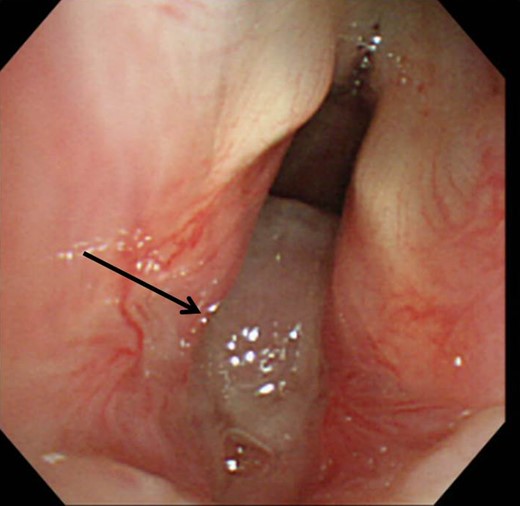

Upon arrival, he complained of severe dyspnea with inspiratory stridor in his throat. Computed tomography revealed a mass arising from the posterior wall of the trachea (Fig. 1). Bronchoscopy revealed a white subglottic tumor occupying 80% of the tracheal diameter (Fig. 2). We performed an emergency tracheostomy under topical anesthesia, and the symptoms improved dramatically. For 5 days after the tracheostomy, hydrocortisone was prescribed; however, no tendency toward reduction of the mass could be identified during follow-up bronchoscopy. To shorten the treatment period, we performed a resection of the tumor under bronchoscopy 6 days after the tracheostomy.

Bronchoscopy revealed a white subglottic tumor occupying 80% of the tracheal diameter (arrow).